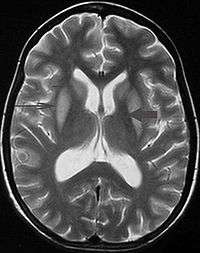

It can be difficult to identify using conventional imaging techniques. It presents more prominently on MRI than on CT, often taking several weeks after acute onset of symptoms before it becomes identifiable. Imaging by MRI demonstrates an area of high signal return on T2 weighted images.